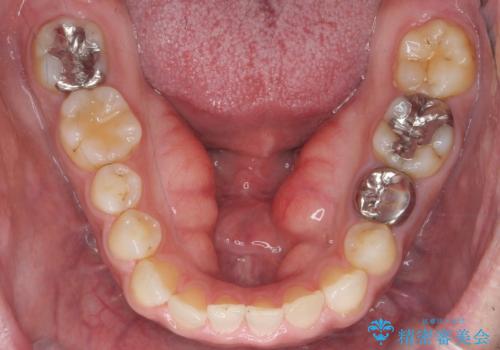

局所麻酔下にて施術しました。

術後1週間で抜糸、約2週間で完全に治癒していきました。

切除後は特にラ行が言いやすくなったそうで大変喜んでいただけました。